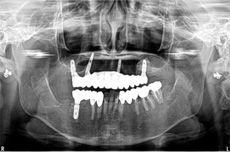

当院で治療された方の症例集をご覧ください!

オールオン4の治療例:1

治療前

治療後

オールオン4の治療例:2

その他 ボロボロ虫歯の症例